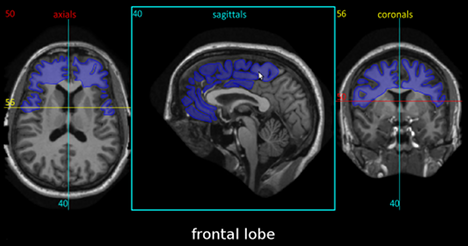

I’ve just found an incredibly use brain anatomy atlas that when you point at any part of an MRI scan it tells you which part of the brain you’re looking at in all three planes.

If nothing else, do check out the MRI atlas as it will give you a feel for how clearly different brain structures appear on a common type of medical scan.

As some folks on the Twitter arguing service have noted, its only slight drawback is the brain’s biggest structure (the frontal lobes) are not perfectly outlined, but they’re marked adequately and it’s still a massively useful tool that I’ve been referring to ever since I found it.